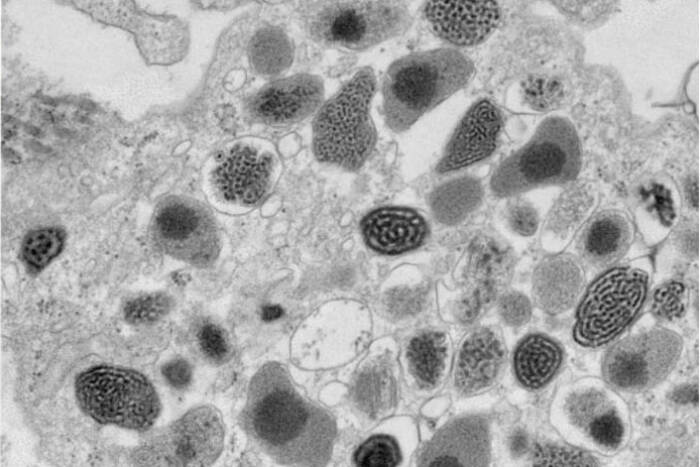

Dr. Amalia Pasolli, Director of the EMRC, and Dr. Anurag Sharma recently co-authored a study in Nature titled “Cellular ATP Demand Creates Metabolically Distinct Subpopulations of Mitochondria,” [1] which uncovers how cellular energy requirements influence mitochondrial dynamics and function. This research demonstrates the adaptive capabilities of mitochondria to segregate metabolic pathways in response to cellular energy demands. The findings, facilitated by the advanced imaging technologies at the EMRC, have profound implications for understanding metabolic disorders and cancer. The full article is available here(opens in new window)

The Electron Microscopy Resource Center boasts a range of sophisticated techniques and tools that enable detailed studies of biological processes. Cryo-Scanning Electron Microscopy (Cryo-SEM) serves as a critical tool for exploring invertebrates, shedding light on the intricate details of their natural environments. Bridging the technological gap, Correlative Light and Electron Microscopy provides a seamless connection between conventional light microscopy and transmission electron microscopy (TEM), allowing researchers to achieve a comprehensive view of cellular activities. For those seeking dynamic insights, 3D TEM Tomography offers a cinematic glimpse into cellular functions, producing vivid “movies” of mitochondria in motion. Additionally, the center employs Immunogold Labeling to precisely target specific antigens within cells, significantly enhancing the detection and detailed study of essential cellular components.